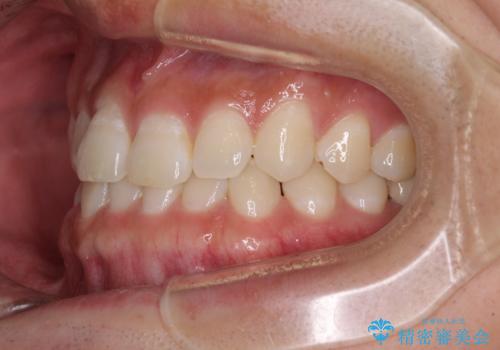

隙間の空いた前歯を治したい 上顎の部分矯正

- 上顎前歯の隙間を気にして来院された患者様です。

下顎前歯に叢生がありましたが、特に気にしていらっしゃいませんでした。

下顎臼歯にインプラント補綴治療がされており、全顎治療するにはクラウンの作り替えが必要となる旨を説明し、ワイヤー装置により上顎のみの矯正治療を行うこととしました。